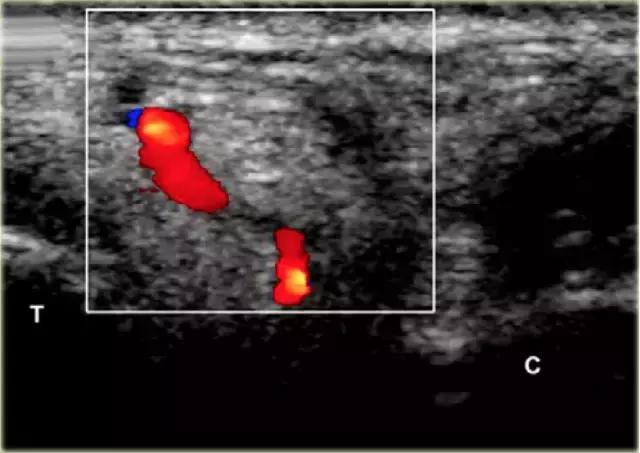

在跗骨窦被识别为跟骨的前处理和距骨颈之间的三角空间。针(箭头)的前端的锥形跗骨窦,这是由距骨(T)和跟骨(C)的边界内可以看到。

根据炎症的程度,可能存在空间的充血,并且可能存在中间血管可见,这是人们希望避免的。但是这又是比较容易的,特别是彩色多普勒。